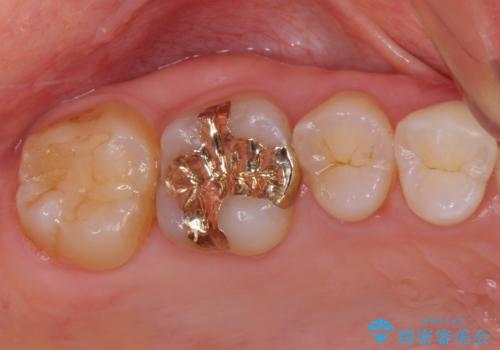

PGA(ゴールド)クラウン、インレーの注意事項(リスク・副作用など)

- インレーおよびクラウンは脱離するリスクがあります

- 形成量はセラミックより少ないですが、歯の形成、修復後に歯に症状が出ることがあります

- 自費診療(保険適用外治療)となります